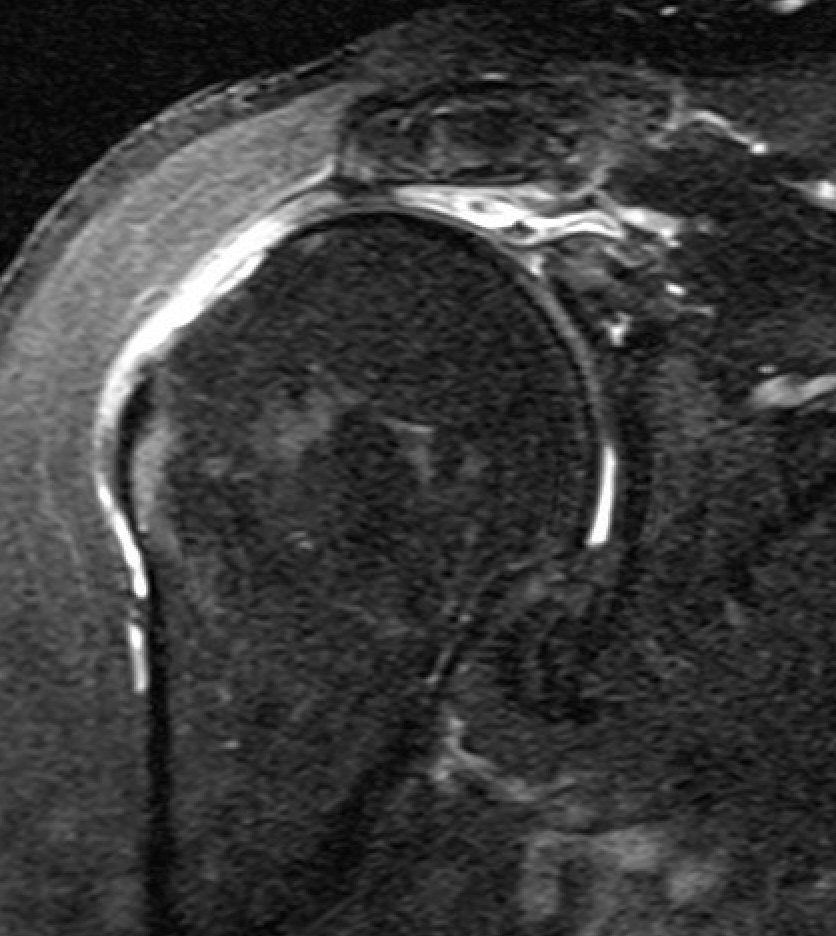

MRI

Measure tear in the coronal and sagittal plane

Massive rotator cuff tear of the supraspinatus and infraspinatus tendon - retracted to glenoid

Supraspinatus atrophy

Tangent sign

- sagittal MRI

- line connecting superior coracoid and superior border scapular spine

- if supraspinatus muscle is below line, there is significant atrophy

- positive tangent sign / significant atrophy associated with larger tears / irrepairable tears

Negative tangent / no atrophy Positive tangent / significant supraspinatus atrophy

Examples of rotator cuff tears that are likeley irreparable